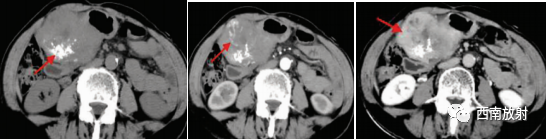

▲间质瘤:女,73 岁,查体发现右上腹软组织肿块。CT平扫见胃窦部向腔内外生长软组织肿块影,大小130 mm×67 mm,其内见多发低密度影及点片状钙化影(箭头);动脉期呈不均匀明显强化,并见强化血管影(箭头)。平衡期呈持续性强化,内低密度影未见强化[4]。